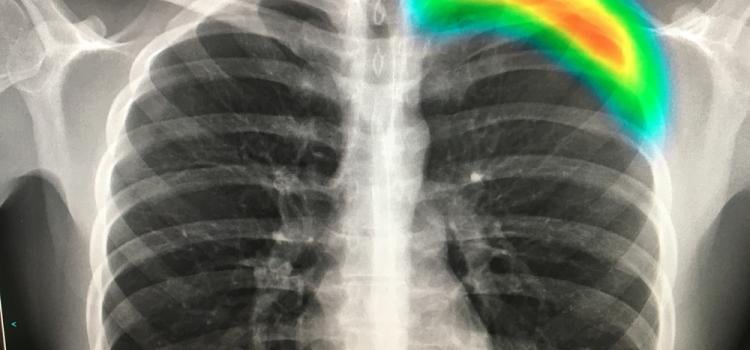

Here are images of some of the newest new medical imaging technologies displayed on the expo floor at the Radiological Society of North America (RSNA) 2019 meeting. Use the slider images below to see the photos.

This gallery includes photos of medical imaging technologies from across the expo floor at the Radiological Society of ...

Here are images of some of the newest new medical imaging technologies displayed on the expo floor at the Radiological ...